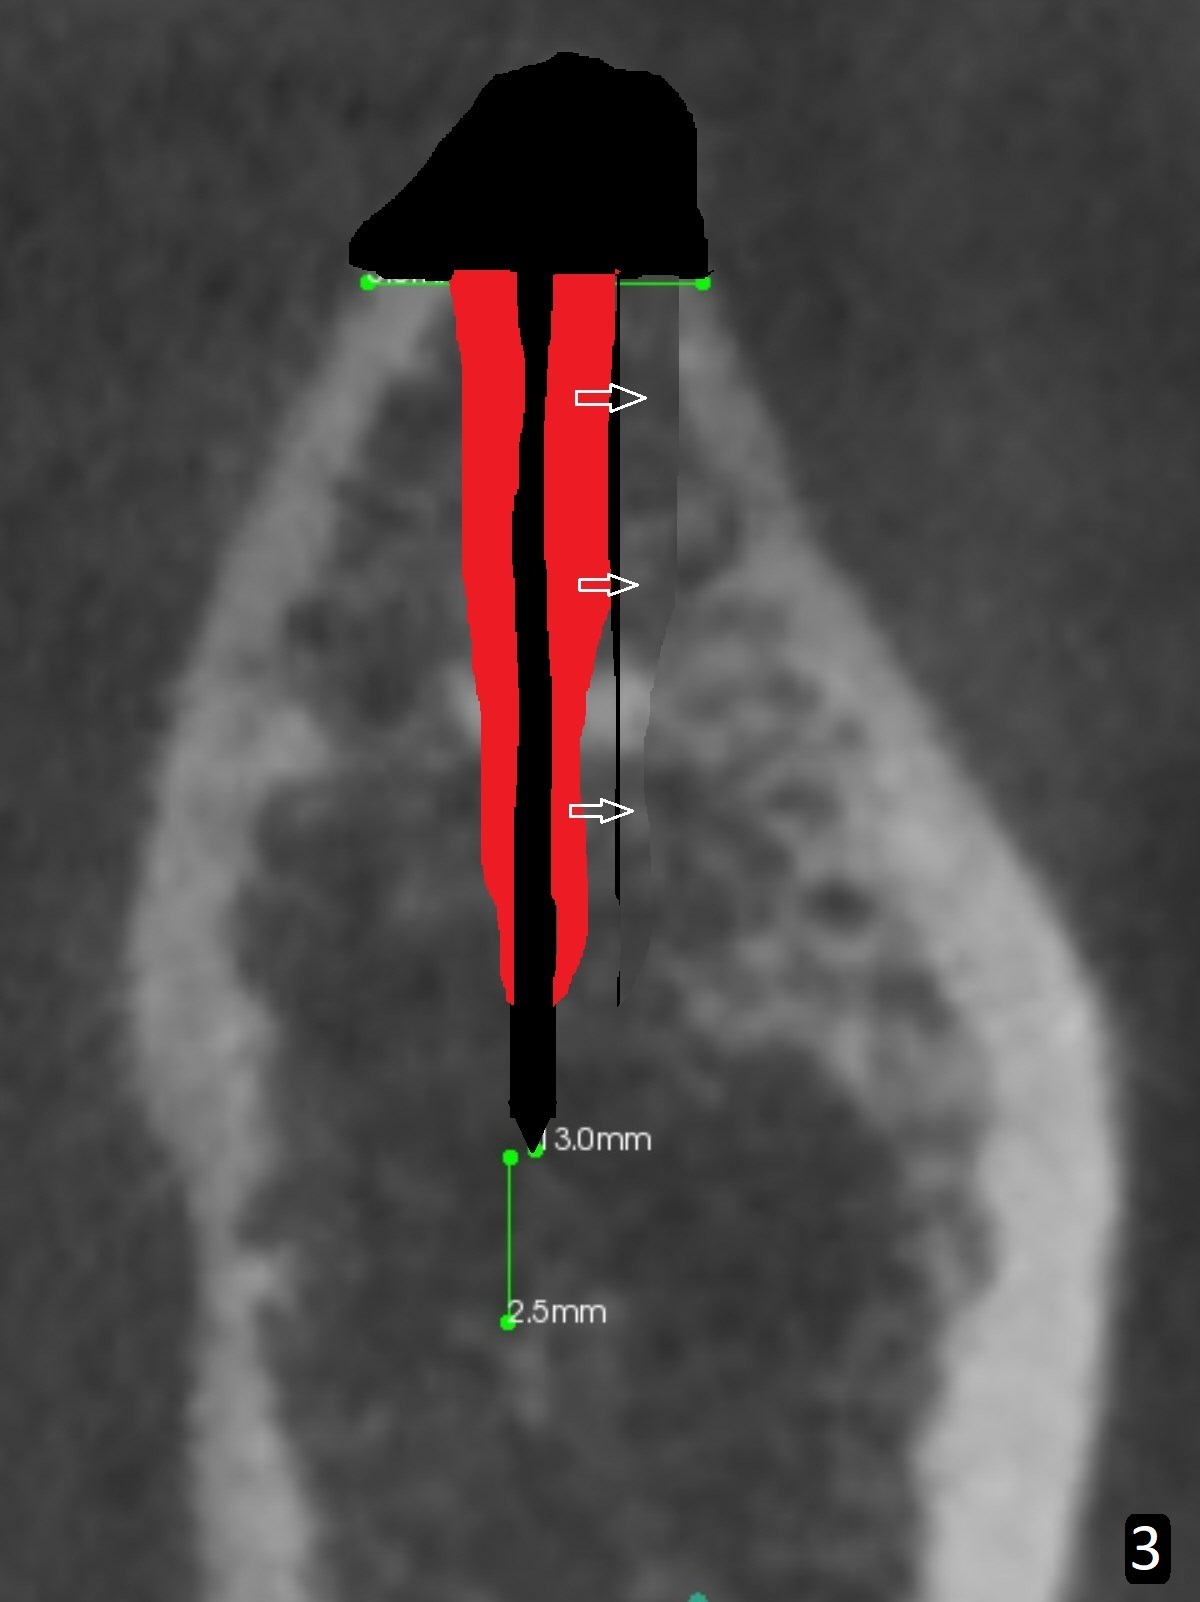

After incision over the narrow ridge at #30 (Fig.1) and ridge reduction (Fig.2 black area on the top; Fig.4 arrowheads), a 1.6 mm drill is used (Fig.2 (CBCT coronal section) long vertical black area) to start BEB (bone expansion and Bending). It is expected that the cortical and cancellous bone of the buccal (B) and lingual (L) plates can be expanded after use of Magic Expanders (ME) and 1.6 mm drill alternatively. In fact it appears that only the cancellous bone is pushed after MEs from 3 to 4.3 mm (Fig.3 arrows). There is no apparent cortical bone bending. There may be cancellous bone condensation. Dummy (Fig.4) and definitive (Fig.5) implants (4x11 mm) are placed. Since torque is 20 Ncm, a 5.5x4 mm healing abutment is placed (Fig.5,6 H). The opposing tooth is supraerupted; intrusion is pending. A 6x4(2) mm abutment is placed with a provisional 2 months postop. There is enough occlusal clearance. Impression is taken 5 months postop with difficulty because of subgingival margin (Fig.7). After cementation, the patient feels discomofort, which is relieved when the mesial embrasure is enlarged. Return to Lower Molar Immediate Implant, Armaments Xin Wei, DDS, PhD, MS 1st edition 12/14/2017, last revision 09/16/2018